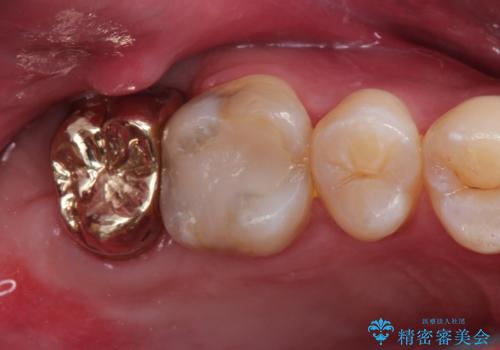

以前の被せもののマージンは歯肉縁下に深く形成され、根尖病変も認めたため、根管治療(林先生に依頼)、歯周外科、PGAクラウンにて修復治療を行いました。

妥協せずにすべての治療を行うことで最終的な被せものの適合を高める事ができます。今回のケースを保険の治療で行う場合は長期予後を望めないものとなります。

PGA(ゴールド)クラウン、インレーの注意事項(リスク・副作用など)